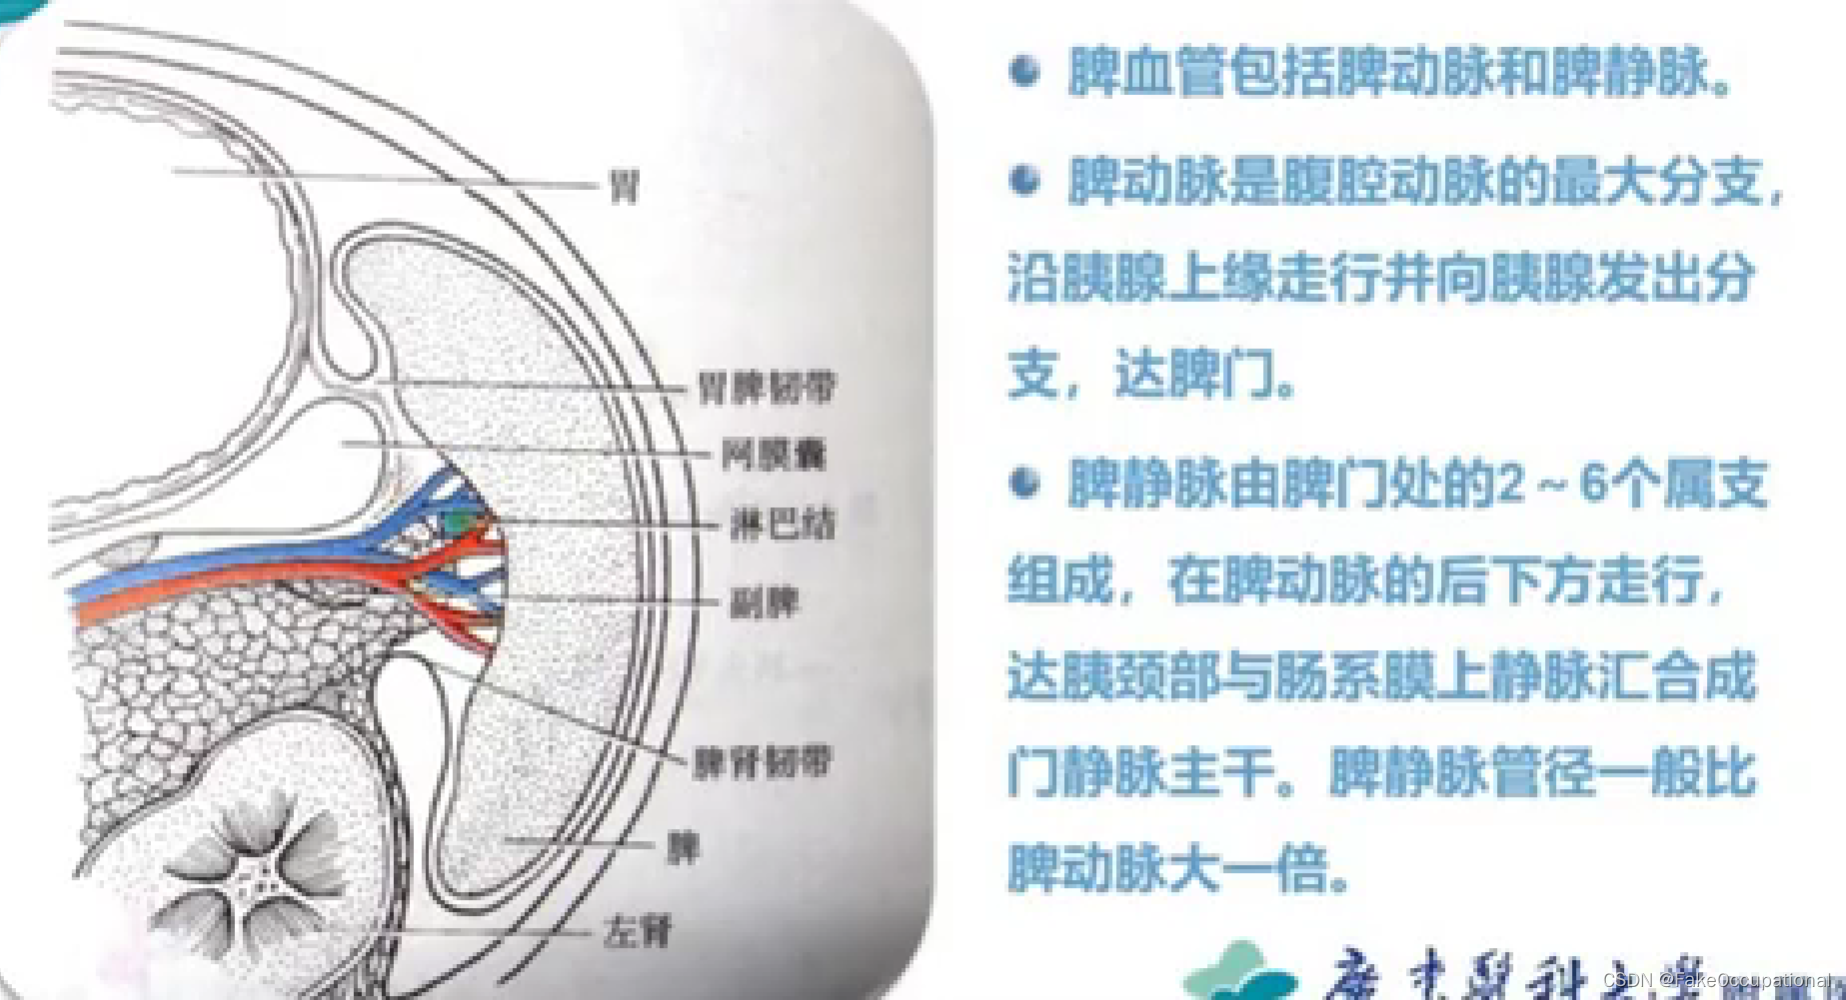

脾脏解剖及正常声像图